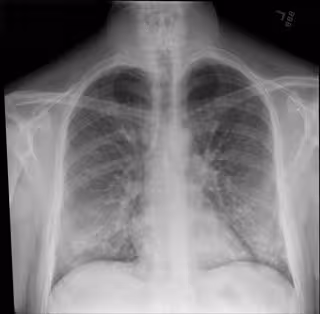

Radiografía de tórax

Radiografía de tórax - INTERMOUNTAIN HEALTHCARE - Archivo

Su investigación parte de la base de que la imagen radiológica permite diferenciar con gran precisión una neumonía provocada por el coronavirus de otros tipos de neumonía. "Usamos un algoritmo de aprendizaje y e inferencia a través redes neuronales convolucionales. Este tipo de algoritmo es muy eficaz para el análisis de imagen porque es capaz de extraer información con varios niveles de detalle, en función del tamaño y resolución de los ficheros de entrada", han explicado.

El modelo ha sido entrenado con cuatro categorías de radiografías: las correspondientes a pacientes con neumonía atribuida a coronavirus, con neumonías víricas y bacterianas y con ambos pulmones sanos, así como una cuarta categoría donde encajan las imágenes fallidas.